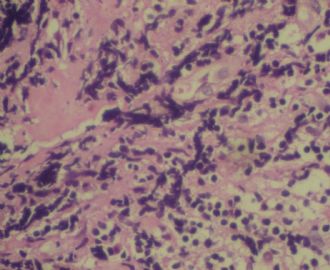

姓    名: ××× 性别:  女 年龄:  77岁

标本名称:  左前臂数个大小不等的皮下肿物。

既往有非何杰金淋巴瘤(滤泡性淋巴瘤)病史22个月。

• 左前臂数个大小不等的皮下肿物     淋巴瘤?图1

图1

病例不错。细胞胞浆透亮,间质血管丰富,图片不是很清晰,似乎有嗜酸粒细胞?

恶性,首先考虑T-NHL。IHC证实。

既往有NHL病史,图片不太清晰,细胞弥漫,胞浆透亮,首先考虑T细胞淋巴瘤。